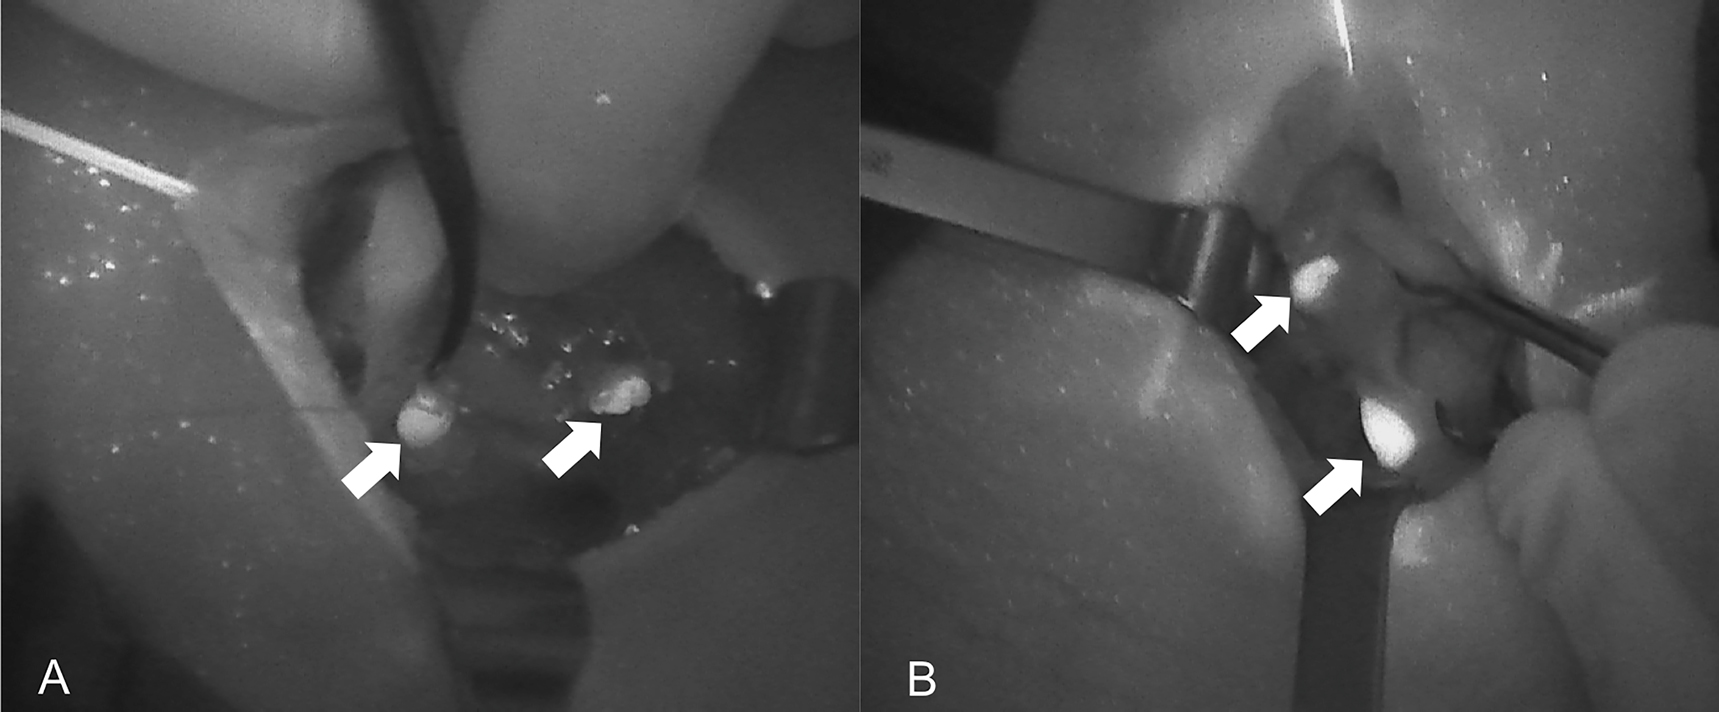

Near-infrared autofluorescence (NIRAF) images of normal parathyroid glands (PGs). Arrows indicate localization of Fluobeam LX. (A) Image of the right side after thyroidectomy. (B) Image of the right side in a case of primary hyperparathyroidism.

Near-infrared autofluorescence (NIRAF) images using Fluobeam LX showing the autofluorescence of the parathyroid glands (PGs). (A) Two PGs after superior pole dissection and the medialization of the right thyroid lobe. (B) Superior PG after medialization of the left thyroid lobe. PGs are indicated with white arrows.